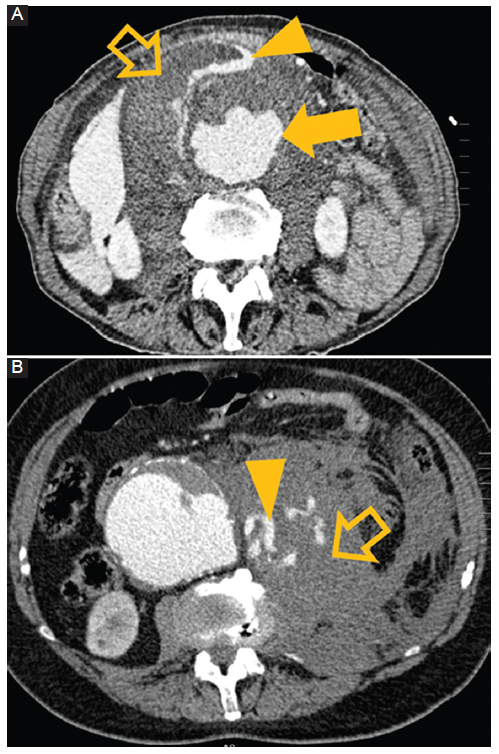

Figura 3

Rotura de un aneurisma. Hombre de 62 años. Dolor abdominal e hipotensión. TC con contraste cortes axiales A y B: se observa un aneurisma aórtico abdominal roto (flecha) con un extenso hematoma retroperitoneal (flecha hueca) y hemorragia activa demostrada por extravasación del medio de contraste (punta de flecha).